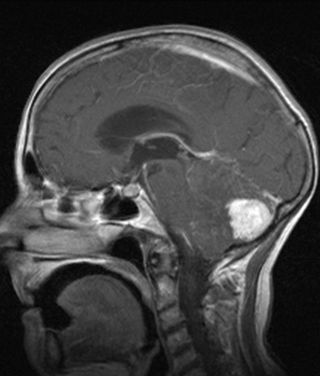

Arnold – Chiari malformation

Type I. the cerebellar tonsil appears pointy and extends below the level of the foramen magnum, but it does not exceed 5 mm.

In Type II. the caudal part of the cerebellum also extends below the foramen magnum while the medulla oblongata and IV. ventricle sink to the widened segment of the spinal canal. It is accompanied by neural tube closing disorders.

Type III is the combination of type II. with occipital cephalocele.

Radiologically they are the best depicted in sagittal (+ coronal) imaging planes.